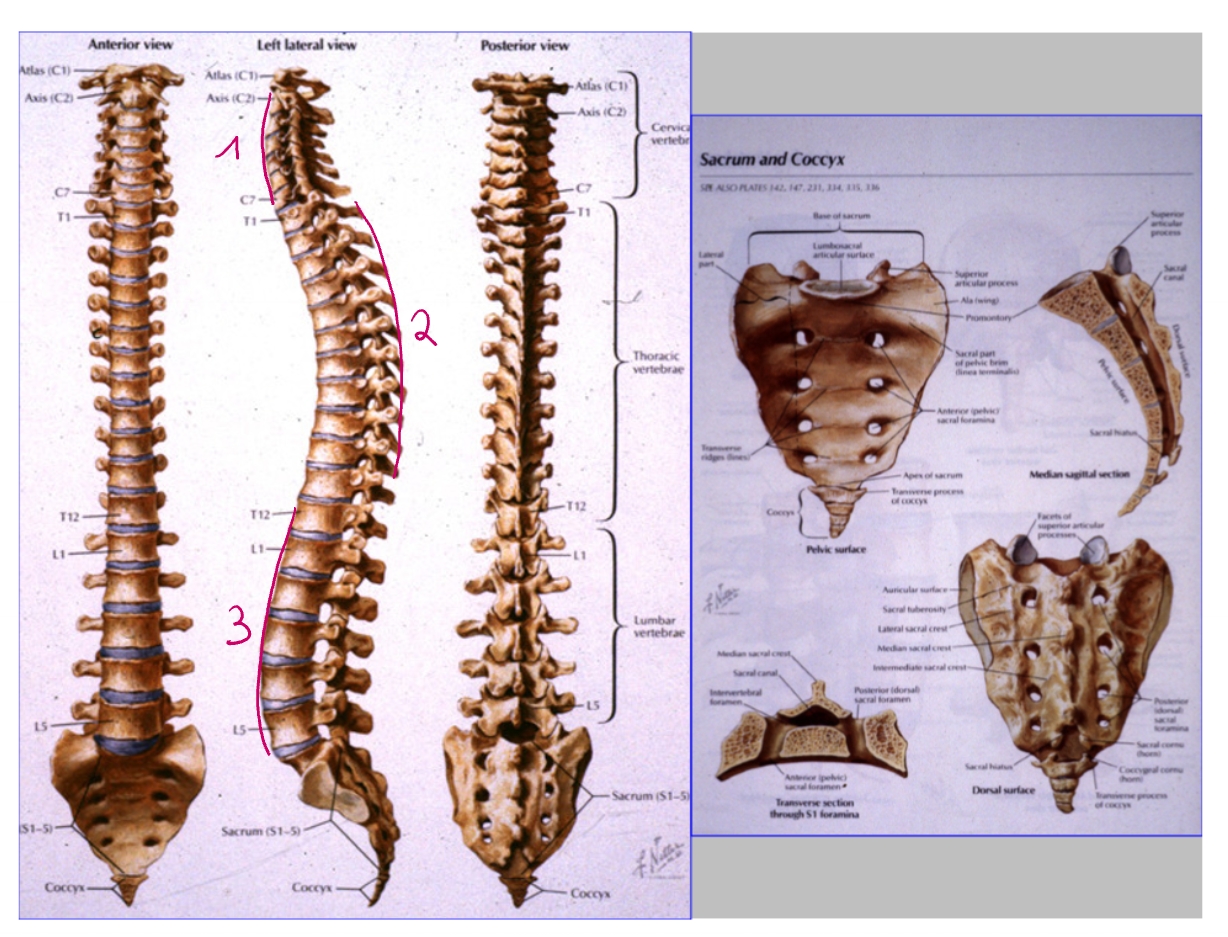

cervicale lordose

thoracale kyphose

lumbale lordose

corpus T12

rib 12

zwevende rib

ala van het sacrum (= de vleugels)

corpus S1